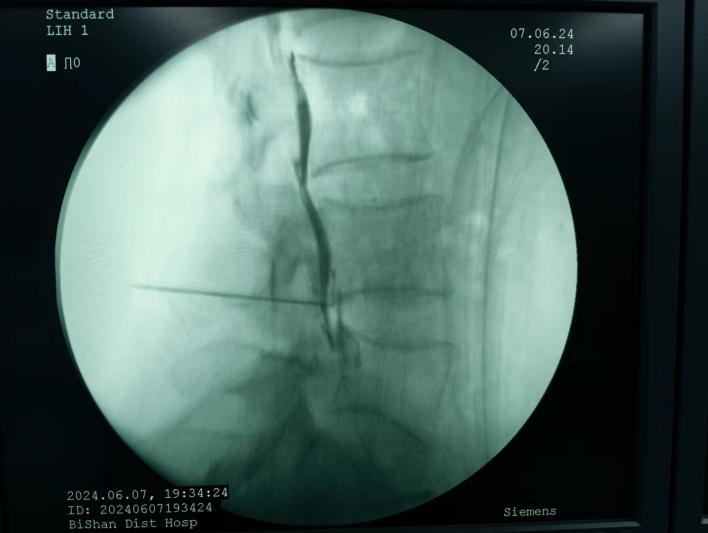

射頻消融治療,連續射頻或脈沖射頻對椎間盤或神經進行干預治療,目的是減小神經根周圍的壓力及對神經的調控治療,從而達到緩解癥狀的效果;

膠原酶椎間盤化學溶解術,是在影像引導下(C型臂X線機或CT),將膠原酶準確地注射到突出的椎間盤內及其周圍,使突出的椎間盤溶解并吸收,解除其對神經根的壓迫,進而緩解癥狀。